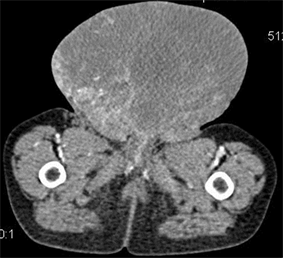

H.G. was a 30 months old boy admitted for the management of a testicular mass fortuitously discovered by the parents at the age of 6 months. It was then a small, painless and rapidly evolving testicular mass. A management had initially been started in a health facility, which consisted of a first excision of the mass that would have been total and a second one six months later as the mass recurred. An orchidectomy had not been performed. The anatomopathological investigation had found a proliferation of multinucleated cells of variable shape with eosinophilic cytoplasm; the desmin, actin and vimentin tests were positive. A pleiomorphic rhabdomyosarcoma had been concluded. He then received seven sessions of unsuitable and unsuccessful chemotherapy (Doxorubicin, Vincristine and Cyclophosphamid). Let’s mention that in the pediatric oncology unit, there was a not yet published cohort wherein the rhabdomyosarcoma proportion was 3.7% with 5 cases out of 132 children. H.G. was admitted at CHUMEL, two years after the disease onset in this context. No particular personal or family history was noted. The patient’s initial clinical examination revealed a general condition not significantly degraded, a normal skin and mucous membranes coloration, a good hydration and nutrition status with a weight of 11 kg. There was no infectious or edematous syndrome. The genitourinary examination revealed a shiny oval scrotal mass, 17 cm × 13 cm in size, a twisted and infiltrated penis, the presence of a left inguinal scar (Figure 1(a) and Figure 1(b)) and a bladder globe. The hepato-digestive examination revealed a fixed oval mass in the left iliac fossa, hard, painless with a regular surface, measuring 03 cm × 2.5 cm. There was no hepatomegaly or splenomegaly. The lymph nodes areas were free. The thoraco-abdominal scan performed as part of the extension investigation (Figure 2(a) and Figure 2(b)) revealed a large intra-scrotal mass measuring approximately 140 × 125 × 127 mm, having an heterogeneous multi-lobulated shape, a tissue (42 HU: Hounsfield Unity) and necrotic (30 HU) components, richly vascularized septa after contrast agent injection that persisted in the late stage; and a mass in the left iliac fossa with multi-lobulated shape, measuring 60 × 54 × 54 mm, heterogeneous, with a hyper-vascularized tissue and necrotic components, with an enhancement kinetics similar to the intra-scrotal mass, latero-deviating the bladder without invading it. No thoracic or bony location was observed. Proof-reading of the slide by another pathologist was consistent with the initial diagnosis of a pleiomorphic rhabdomyosarcoma. The tumor was classified as stage II (TNM) and had a poor prognosis (location, size, initial resection and

(a) (b)

Figure 2. Thoraco-abdominal CT scan ((a) transverse section of scrotal mass; (b) sagittal section).